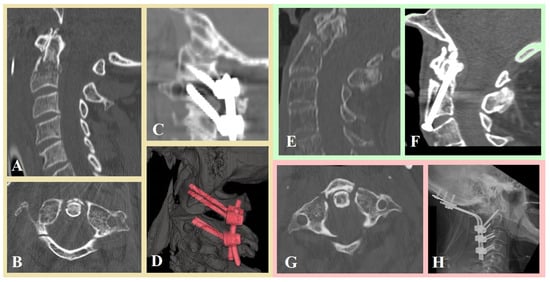

- Montemurro, N.; Carnesecchi, S. Is Direct Transpedicular C2 Fixation (Judet Approach) a Timeless Technique to Learn for C2 Fractures? Glob. Spine J. 2025, 11, 21925682251367412. [Google Scholar] [CrossRef]